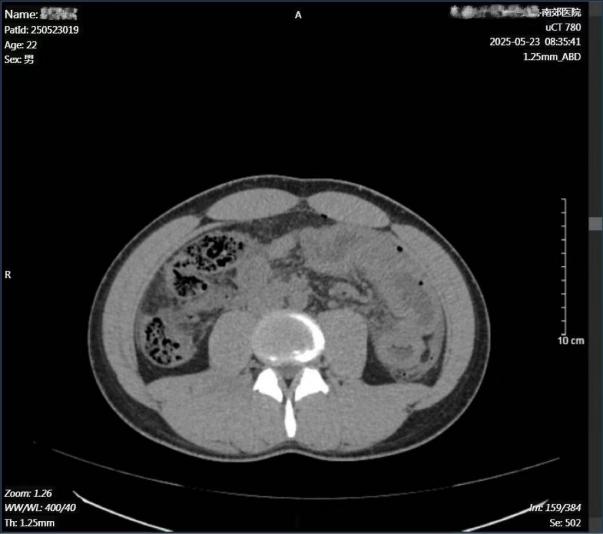

经普外科会诊,再次CT检查考虑是空腔脏器破裂导致的严重腹膜炎,查血常规白细胞为29.98×10^9/L。普外科王兆太主任团队为其制定了详细的手术方案,并为可能出现的突发状况制定了预案。在麻醉科、手术室等科室的通力合作下,为伤者进行了腹腔镜手术。

术中探查,腹腔大量浑浊液体约1000ml,重度感染,距离屈氏韧带约35cm处空肠见直径约1.5cm的穿孔,肠液及食物残渣不断渗出,另见部分小肠浆膜及左半结肠浆膜及脂肪垂挫伤。给予肠壁修补,大量生理盐水冲洗。手术过程中出血仅10ml。腹壁只有三个小孔,微创手术解决病人创伤难题。